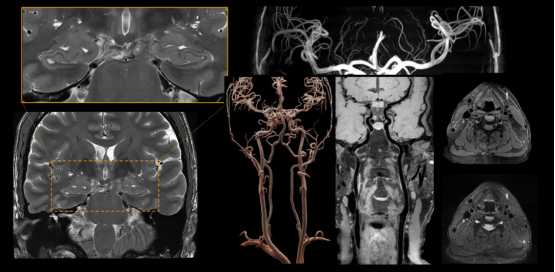

▼超高分辨脑部结构功能成像▼

可进行头部、腹部、膝关节、胰腺等部位的超高分辨扫描,应用于烟雾病、帕金森病、脑肠轴、心源性卒中、肌萎缩侧索硬化(渐冻症)等的临床研究,呈现更丰富的细微结构,更精准的定量分析,助力全身疾病超早期发现。

相较于3T,5T全身高分辨率、高对比度、高信噪比能提供丰富的组织结构和功能信息,有利于精细结构、微小病灶的评估,也有利于因组织功能改变、疾病发展、疾病治疗而产生的结构及功能微小变化的捕捉,可更好地助力脑科学、神经认知科学、发育、代谢、疾病机制及治疗方案探索等方面的相关研究。

5T磁共振成像系统,既充分发挥了超高场磁共振高信噪比、高分辨率、高灵敏度等优势,又有效地解决了超高场带来的图像均匀度、成像安全性等问题,兼具高场强脑功能、微结构评估的优势和全身成像高解析度成像的优势。